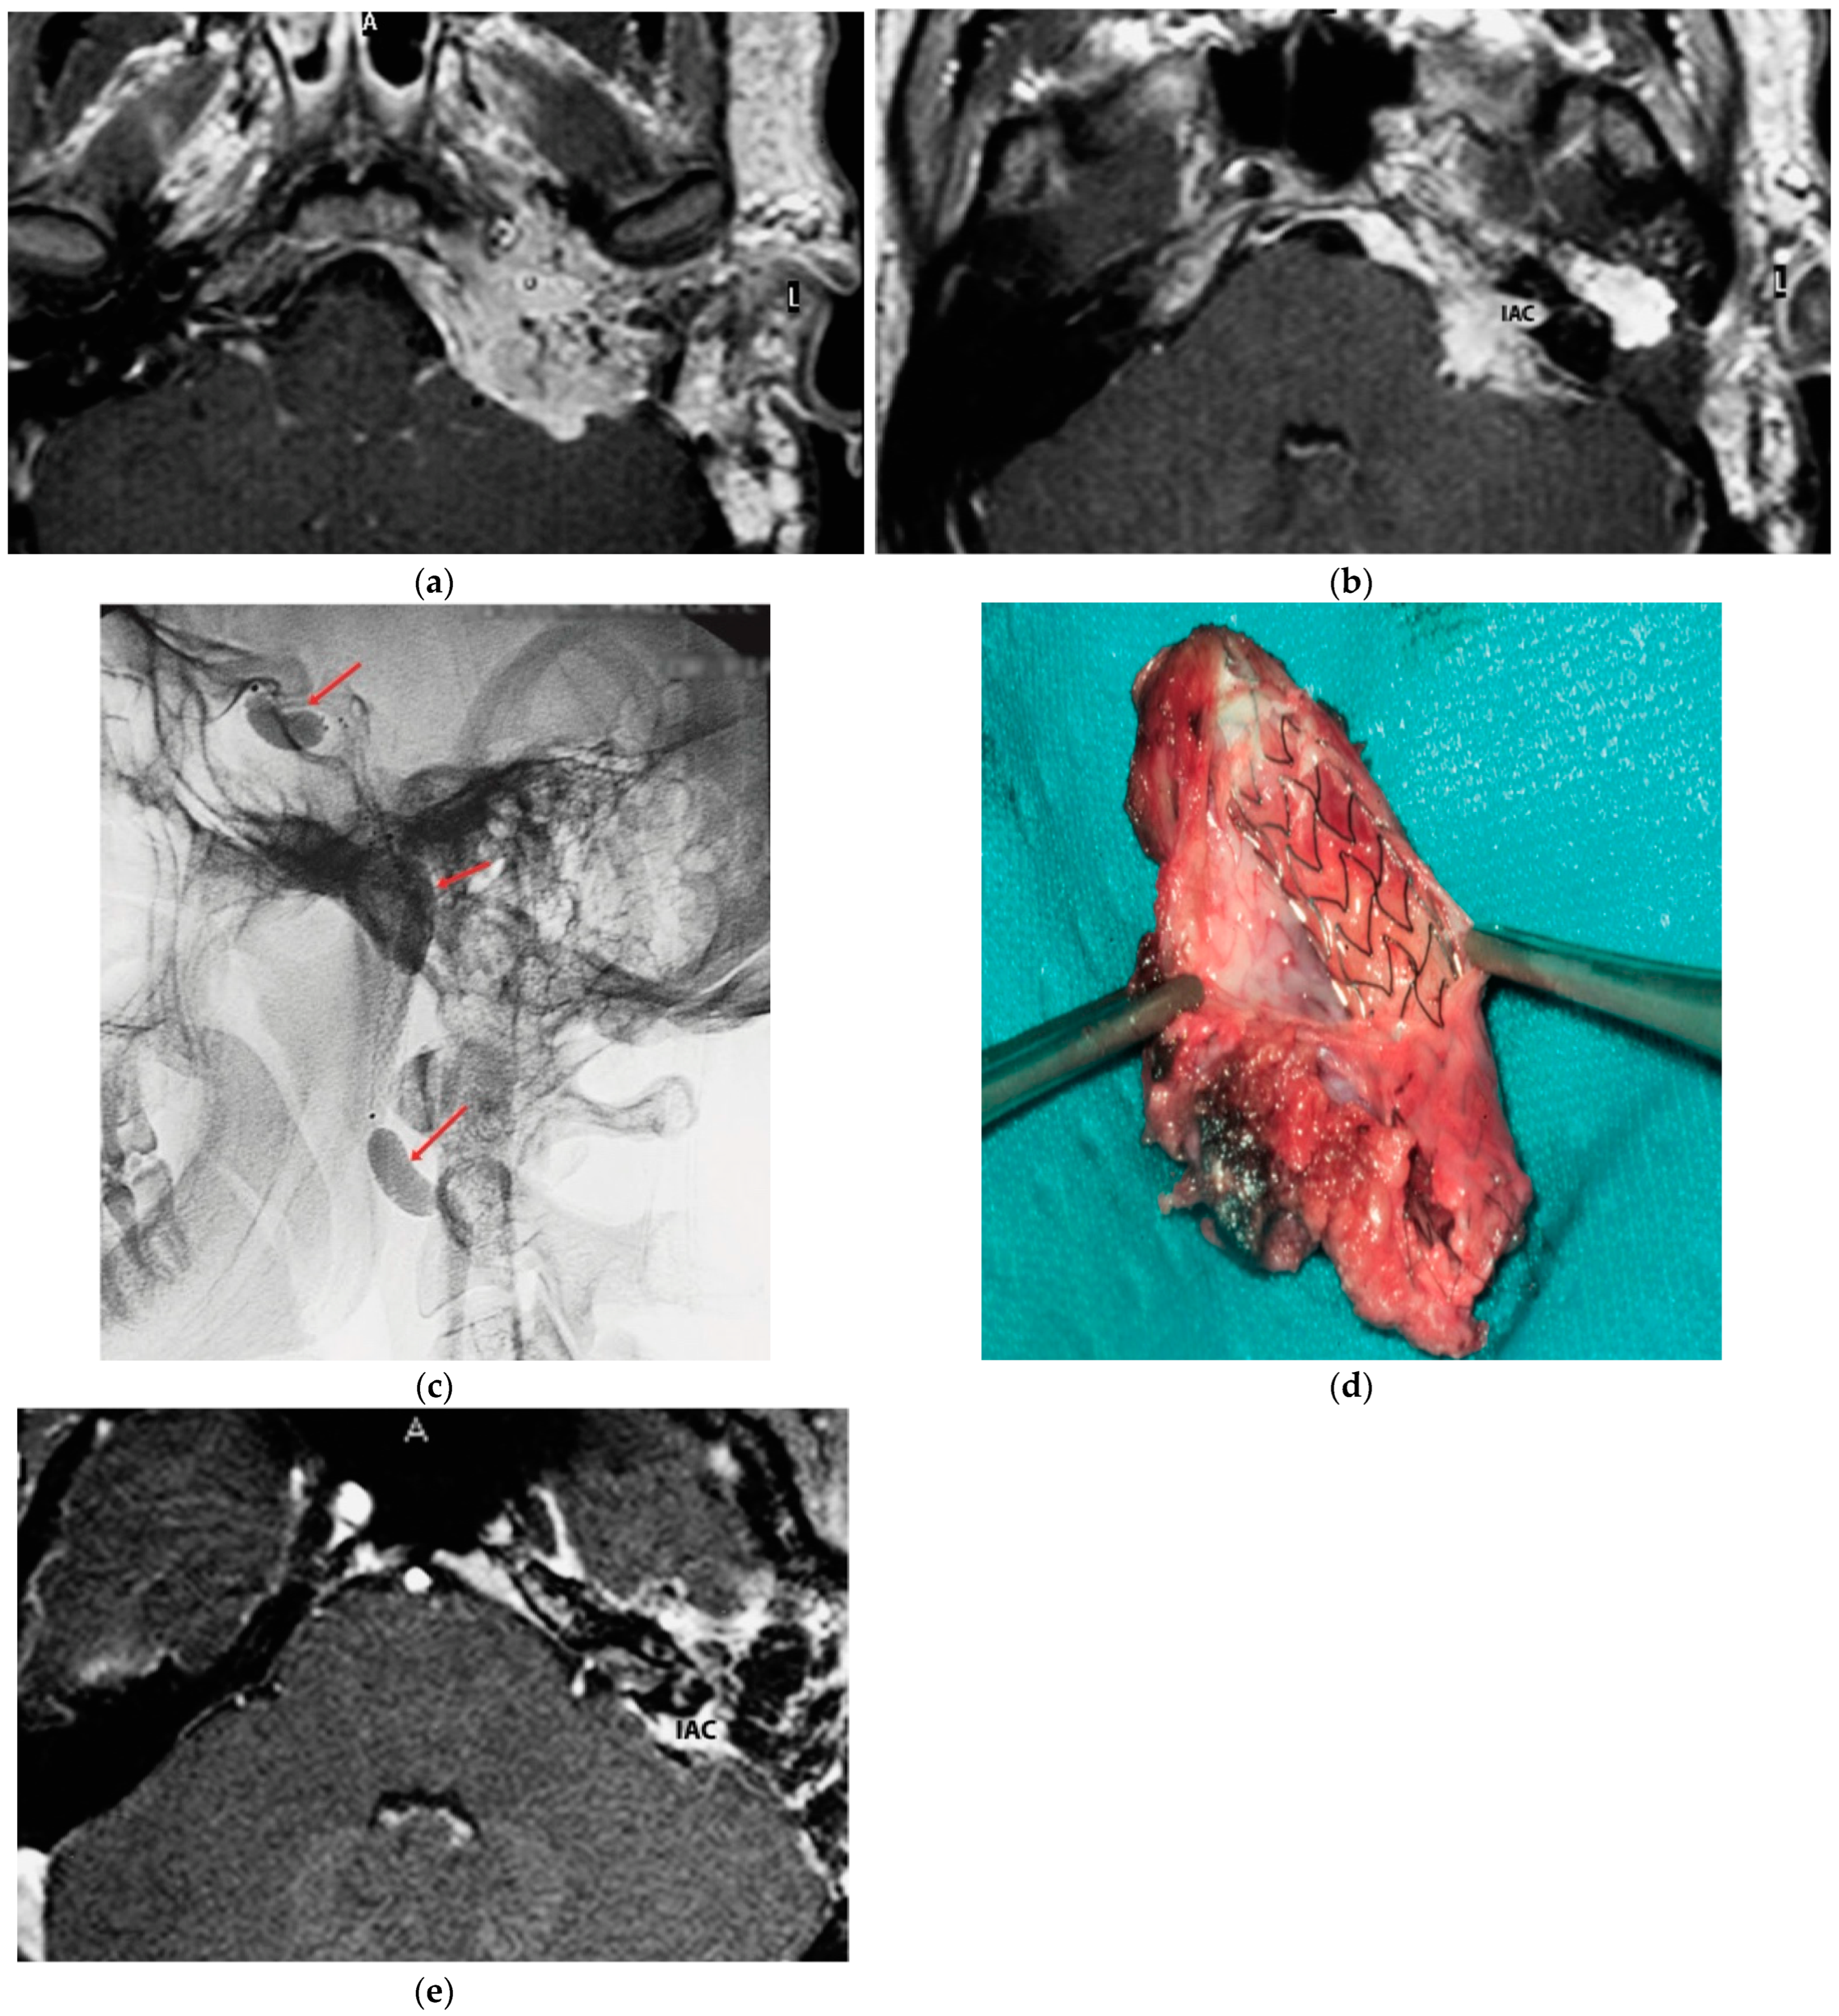

5.5. Case 5: (C3Di2Vi)

5.6. Case 6: (C4Di2Vi)

| 5 | 53 | M | R | X, XI, and XII | C3Di2Vi | Radiation therapy | Embolization |

| IX | Total | 35 |

| 6 | 41 | M | R | XII | C4Di2Vi | 1 surgery in 2002 | Embolization |

| IX, X, and XI | Residual gamma knife (stable) | 145 |